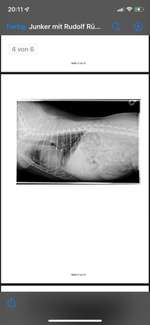

Hallo, mein Hund hat eine Niereninsuffizienz und bekommt 2 x täglich Pronefra. Innereien zu füttern, soll man meines Wissens nach, dabei vermeiden. Da er aufgrund der Nierenproblematik aber eh schon ziemlich mäkelig beim Fressen ist aber gerne Hühnermägen und auch -herz frisst, möchte ich gerne wis ...